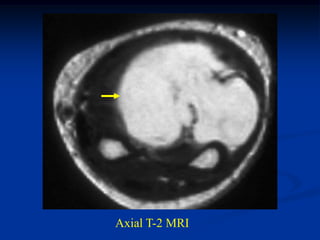

Axial T-2

vessels

Axial Gad